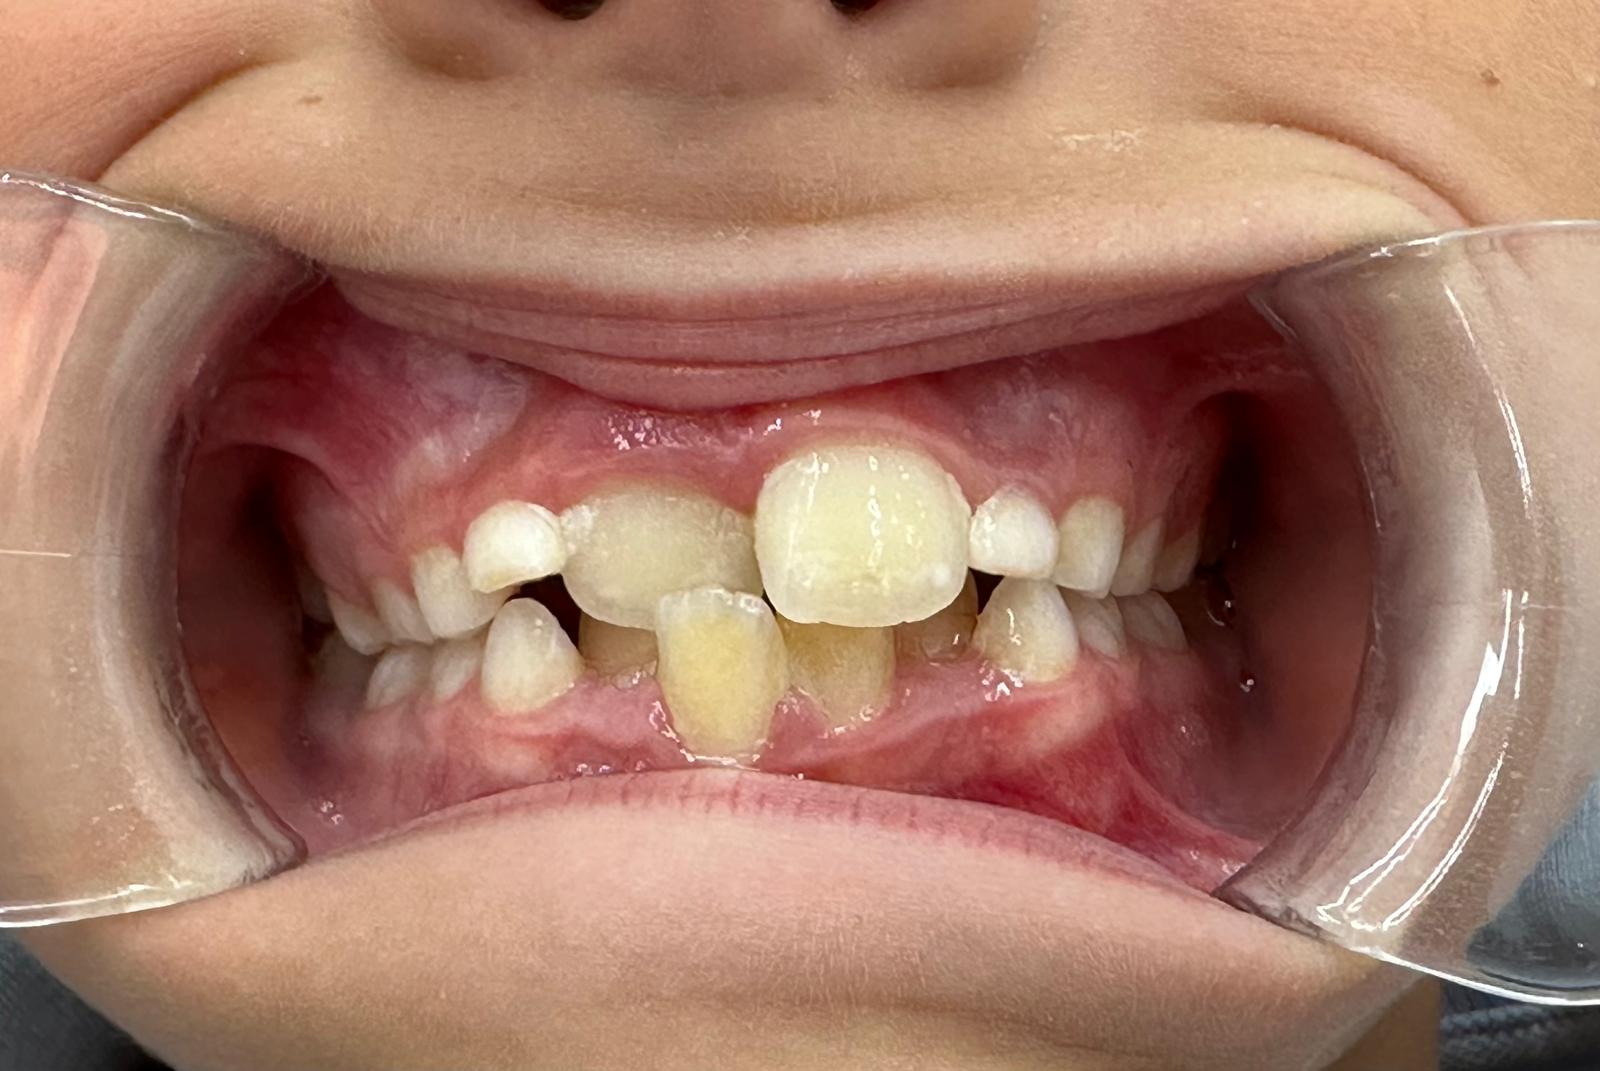

Intervención temprana en crecimiento para corregir mordida y desarrollo óseo

Martín acudió a consulta en fase de crecimiento con una alteración en la mordida anterior.

Los incisivos estaban bloqueando el desarrollo normal de los maxilares, lo que impedía que el crecimiento óseo siguiera su curso natural. Si no se intervenía a tiempo, este problema podía derivar en alteraciones más complejas en el futuro.

Tras realizar el estudio clínico y el análisis digital, se confirmó:

— Mordida cruzada anterior

— Bloqueo del crecimiento maxilar

— Falta de espacio para la correcta alineación dental

— Alteración funcional asociada a la respiración

Nos encontrábamos ante un caso en el que el momento de intervención era clave.

Fase 1 – Bloqueo

Fase 2 – Descruce

Fase 3 – Expansión

Fase 4 – Alineación